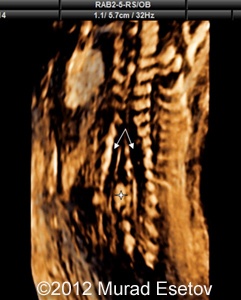

Image 1  shows a coronal section of the thoracic and lumbar spine with spina bifida. Note the widening of the spine and echoic septum (arrow) in the middle of the spinal canal.

Image-1